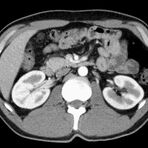

Abdomen (Bauch und Becken)

• Diagnostik von entzündlichen und tumorösen Erkrankungen der Bauchorgane

• Diagnostik von akuten Notfällen wie Darmverschluss, Hohlorganperforation oder Traumafolgen

• Darstellung der großen Gefäße zur Erkennung von Gefäßverschlüssen (z. B. Mesenterial - Arterienembolie oder Einengungen von Gefäßen (z. B. Nierenarterien)

• Darstellung und Therapieplanung von Aneurysmen (CT- Angiographie)

• Virtuelle Kolonographie zur Darstellung des Dickdarmes z. B. bei Kontraindikation zur Darm-Spiegelung oder nur unvollständig durchführbarer Koloskopie.